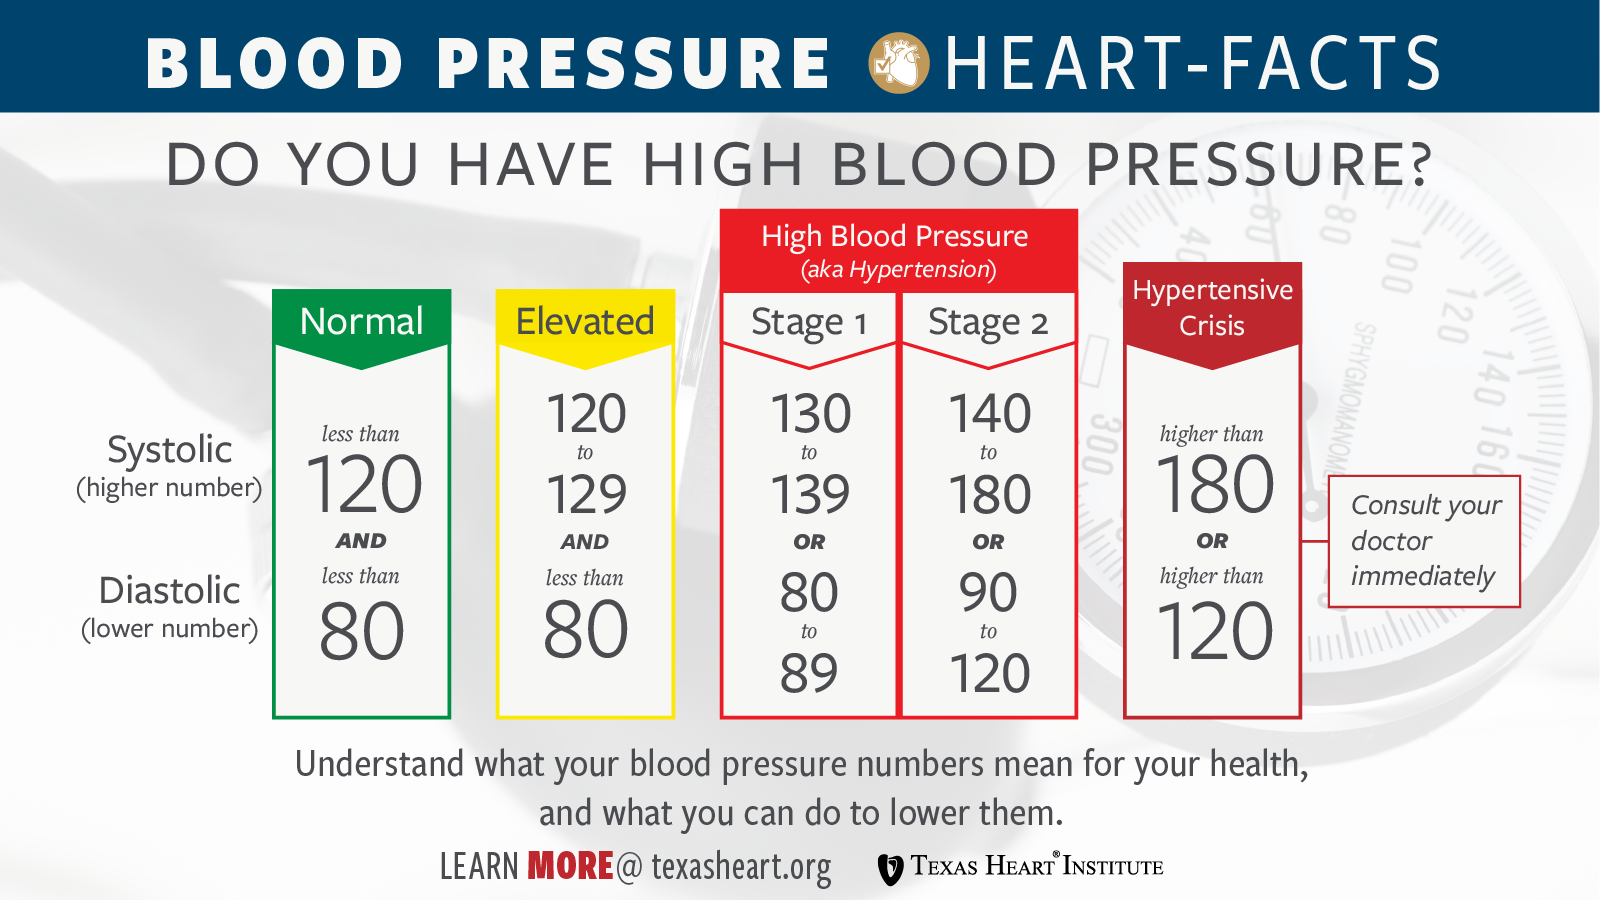

High Blood Pressure Hypertension Texas Heart Institute

Why Does Systolic Blood Pressure Increase With Age Increased Systolic